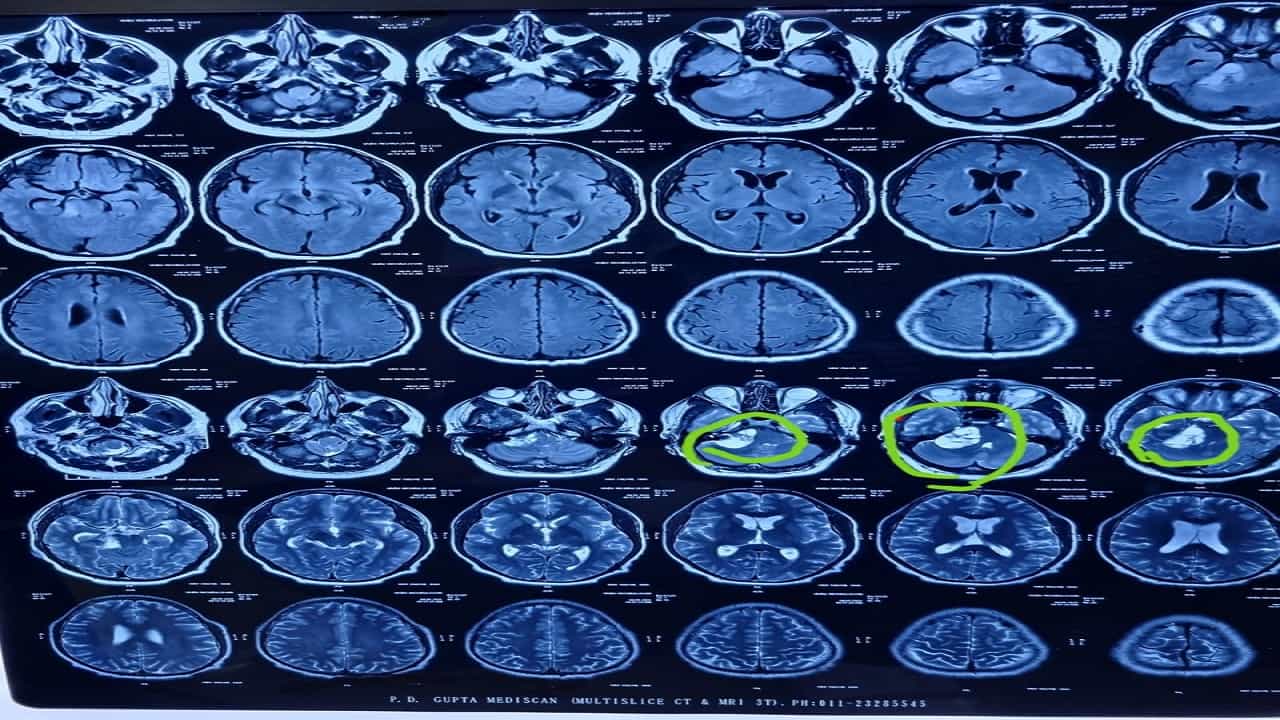

मीरारोड येथील वोक्हार्ट हॉस्पिटलचे न्यूरोसर्जन डॉ. विनोद रामबल म्हणाले, रुग्णाच्या भावाने सर्वप्रथम न्यूरोसर्जनची भेट घेतली आणि रुग्णाच्या प्रकृतीविषयी समजावून सांगितले. एमआयआय तपासणीत रुग्णाच्या कवटीत गाठ आढळून आली. ही गाठ मज्जातंतूतून उद्भवते. जे आपल्या शरीरावर नियंत्रण ठेवते. समतोल आणि मुद्रा, ज्यामुळे चेहरा सुन्न होणे, वजन वाढणे आणि ऐकण्यात अडचण येणे अशा समस्या निर्माण होतात.

डॉ. रामबल पुढे म्हणाले, वैद्यकीय तपासणीत रुग्णाला वेस्टिब्युलर श्वाननोमा असल्याचे निदान झाले. जो एक सौम्य क्रॅनियल नर्व्ह ट्यूमर आहे जो एखाद्याच्या कानामागील 8 व्या क्रॅनियल मज्जातंतूपासून उद्भवतो. तो या नसामधून बाहेर पडतो आणि सुरुवातीला वाढतो, पुढे जातो. ब्रेन स्टेम, मिड ब्रेन आणि पॉन्स हे मेंदू आणि पाठीचा कणा यांना जोडणारे महत्त्वाचे जंक्शन आहेत. ज्याद्वारे मेंदूची क्रिया घडते. अशा प्रकारे सुमारे 2 दशलक्ष घटना घडतात आणि सामान्यतः अधिक रुग्ण 50 ते 60 वयोगटातील दिसतात. ही गाठ शस्त्रक्रियेने काढणे हे एक मोठे आव्हान होते. कुटुंबाच्या संमतीने ही शस्त्रक्रिया करण्यात आली. ही शस्त्रक्रिया सुमारे 6 तास चालली. आठवड्याभरानंतर रुग्णाच्या तब्येतीत सुधारणा पाहून त्याला डिस्चार्ज देण्यात आला.